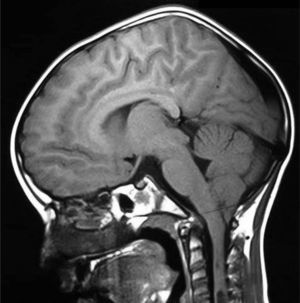

Se realizó una gammagrafía ósea de pelvis y MMII (fig. 1) sin alteraciones en caderas, mostrando menor captación derecha. Ante la sospecha de un proceso con afectación crónica del lado derecho, se realizó resonancia magnética cerebral y medular (figs. 2 y 3) y se diagnosticó de malformación de Arnold-Chiari tipo 1 (MCI) y siringomielia extendida hasta T8. El paciente fue derivado para intervención neuroquirúrgica que resultó exitosa.